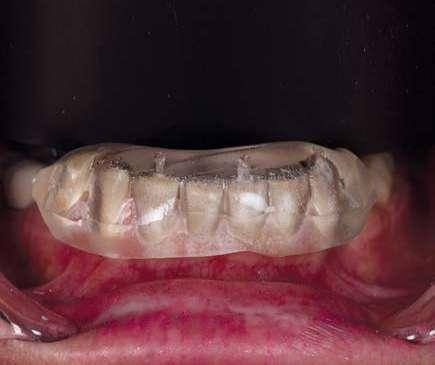

A continuación, presentamos el caso clínico de una paciente con unos dientes mal posicionados y con una coloración acentuada sobre todo a nivel de los centrales que además presentaban extensas restauraciones antiguas de composite en interproximal cerrando diastemas que originalmente presentaba la paciente. Estos dientes necesitarán tener una preparación un poco más subgingival y también removido previamente todo el composite antiguo con el objetivo de camuflar este cambio de color y evitar zonas visiblemente no estéticas.

Como podemos observar la paciente tenía un sustrato muy desfavorable, con un color aproximado de A3,5 Vita.

En la arcada superior por el contrario se decidió poner unas carillas de disilicato para poder cubrir las expectativas de la paciente y ajustar el color al que ella deseaba, bajando casi en 5 tonos el color final. Se planificaron preparaciones digitales conservadoras.